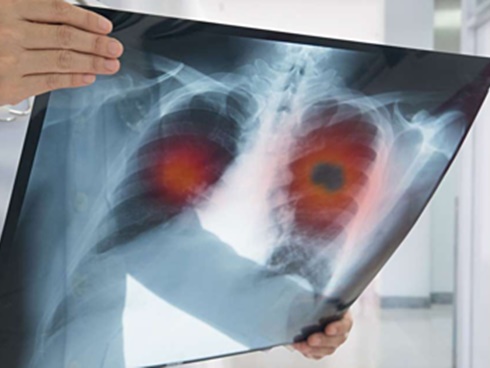

Từ hình ảnh X-quang, bác sĩ nói phổi của cô có màu trắng lớn, đó là viêm bạch huyết ung thư, có nghĩa là ung thư phổi di căn. Thật đáng tiếc khi không còn thời gian để phẫu thuật và hóa trị. Chỉ trong 5 ngày, hơi thở của Tiểu Mơ ngày càng yếu đi và qua đời